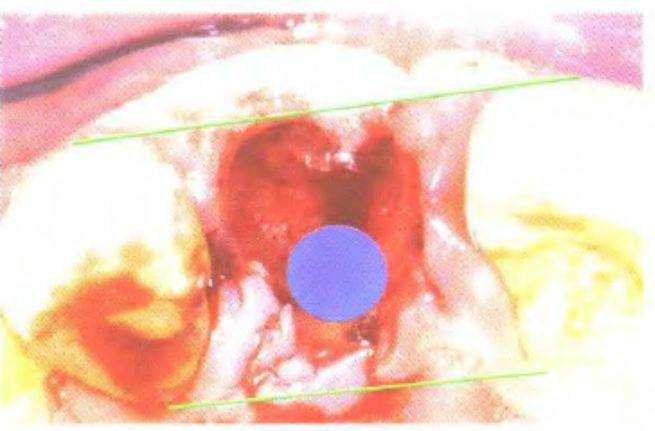

Рис. 3-39z. Вид после второго хирургического этапа имплантации. Рецессия вестибулярной костной стенки (на момент установки имплантатов автор не был знаком с концепцией «эстетического окна»).

кости обычно соответствует классу D3, что подтвердилось в ходе операции. После установки имплантатов ушили края раны и сделали контрольную рентгенограмму (рис. 3-39х и 3-39у). На втором хирургическом этапе имплантации установили формирователи десны (рис. 3-39z). В данном случае при протезировании использовали угловые абатменты и металлокерамические коронки (рис. 3-39z и 3-39аа).